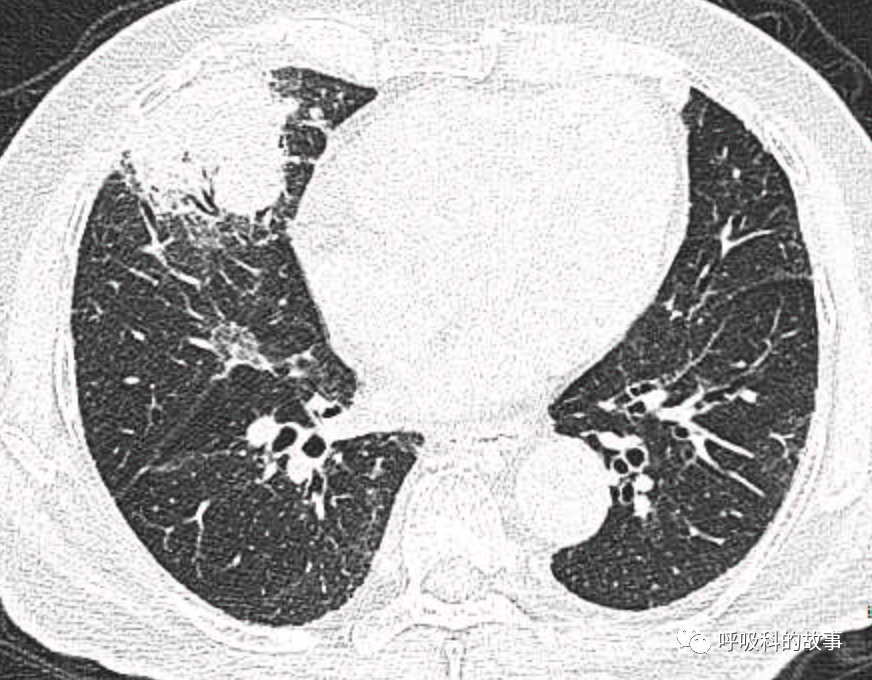

可是就在今年初,患者曾住在某院某科室,因为其他内科疾病住院。当时肺部CT也发现了在右中叶内侧段的高密度实变影,由于影像很类似肺炎,因此当成肺炎治疗。

图12-14:该患者各个角度的影像图像

(上下滑动查看全部图片)